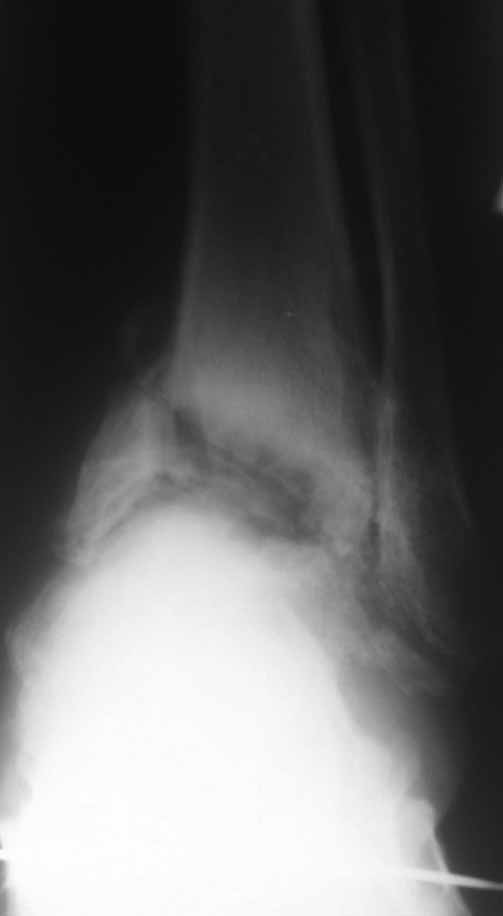

Re: Дефартроз голеностопа+перелом пилона+перелом тарана?

Жалобы со стороны второго сустава есть - прыгать на костылях до томографа без опоры на левую стопу пациенту было больно.

Зачем вытяжение - эффект на рентгенограммах виден.

Склоняемся к мысли, что все таки Charcot's Joint.

Планируем артродез стержнем правого голеностопа + аппарат на левый голеностоп.

Остается вопрос - как монтировать ? одномоментно корректировать или все таки постепенно аппаратом?